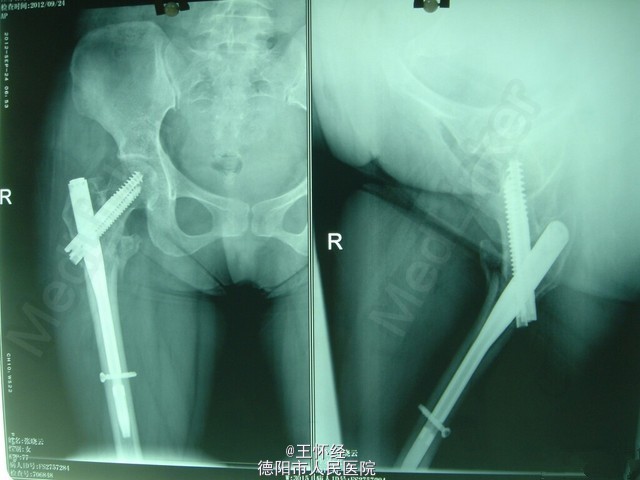

右侧股骨转子间骨折

患者女性,28岁,车祸伤急诊入院,右腿疼痛不能活动,x线检查发现转子间骨折。

右股骨转子间骨折

右侧转子间骨折